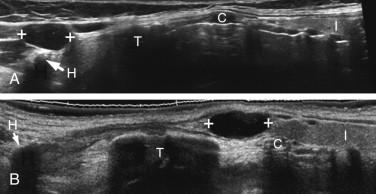

Thyroglossal duct cysts are the most common of the congenital cysts in the neck. During embryogenesis, the thyroid anlage migrates from the foramen cecum of the tongue to the lower neck, leaving an epithelial tract called the thyroglossal duct. This normally involutes in the eighth week of fetal life. Thyroid cells remain in the thyroglossal duct in 5% of cases and can give rise to thyroglossal duct cysts. Despite the embryogenesis, thyroid tissue is usually not detected pathologically in resected specimens. Thyroglossal duct cysts are typically located in the midline between the thyroid gland and the hyoid bone ( Fig. 10-3 ). Approximately 65%, 15%, and 20% occur below, at, and above the level of the hyoid, respectively. Patients most often present in childhood or young adulthood. Sonographically, thyroglossal duct cysts usually appear as somewhat complex cystic lesions with low-level intraluminal reflectors, scattered septations, solid-appearing regions, or irregular walls ( Fig. 10-4A to C ). The more caudal the cyst is located, the more likely it is to be lateral to the midline (see Fig. 10-4D ). It is uncommon for thyroglossal duct cysts to appear completely simple.

F igure 10-3, Thyroglossal duct cysts. Longitudinal panoramic views in different patients show the thyroid isthmus (I), cricoid cartilage (C), thyroid cartilage (T), and hyoid bone (H). A, Thyroglossal duct cyst (cursors) is located in the typical location anterior to the hyoid bone. B, Thyroglossal duct cyst (cursors) located in an infrahyoid location.

F igure 10-4, Thyroglossal duct cysts (cursors) in different patients. A, Longitudinal view of the midline of the neck in the suprathyroidal region shows the hyoid bone (H) and the tracheal cartilage (T) with their associated shadows. A complex cystic lesion with diffuse low-level echoes and comet-tail artifacts is seen located immediately between these two structures. This is the typical location for a thyroglossal duct cyst. B, Similar view in a different patient shows a cyst with a small solid component (arrow) . C, Similar view in a different patient shows a complex cystic lesion with low-level echoes and a thin septation. D, Transverse view of the neck above the level of the thyroid gland shows the thyroid cartilage (arrowheads) . Extending from the midline over to the left is a thyroglossal cyst with diffuse low-level echoes. E, Longitudinal view shows a thyroglossal duct cyst with a large solid component containing scattered microcalcifications confirmed to be papillary thyroid cancer. F, Longitudinal view shows a thyroglossal duct cyst with irregular eccentric wall thickening confirmed to be squamous cell cancer.

Thyroglossal duct cysts are complicated by malignancy in approximately 1% of cases. Ninety-five percent of malignancies are papillary thyroid cancer and the rest are squamous cell cancer. Both most often appear as cystic lesions with substantial solid components in the form of mural nodules, irregular wall thickening, or multiple thick septations (see Fig. 10-4E and F ).